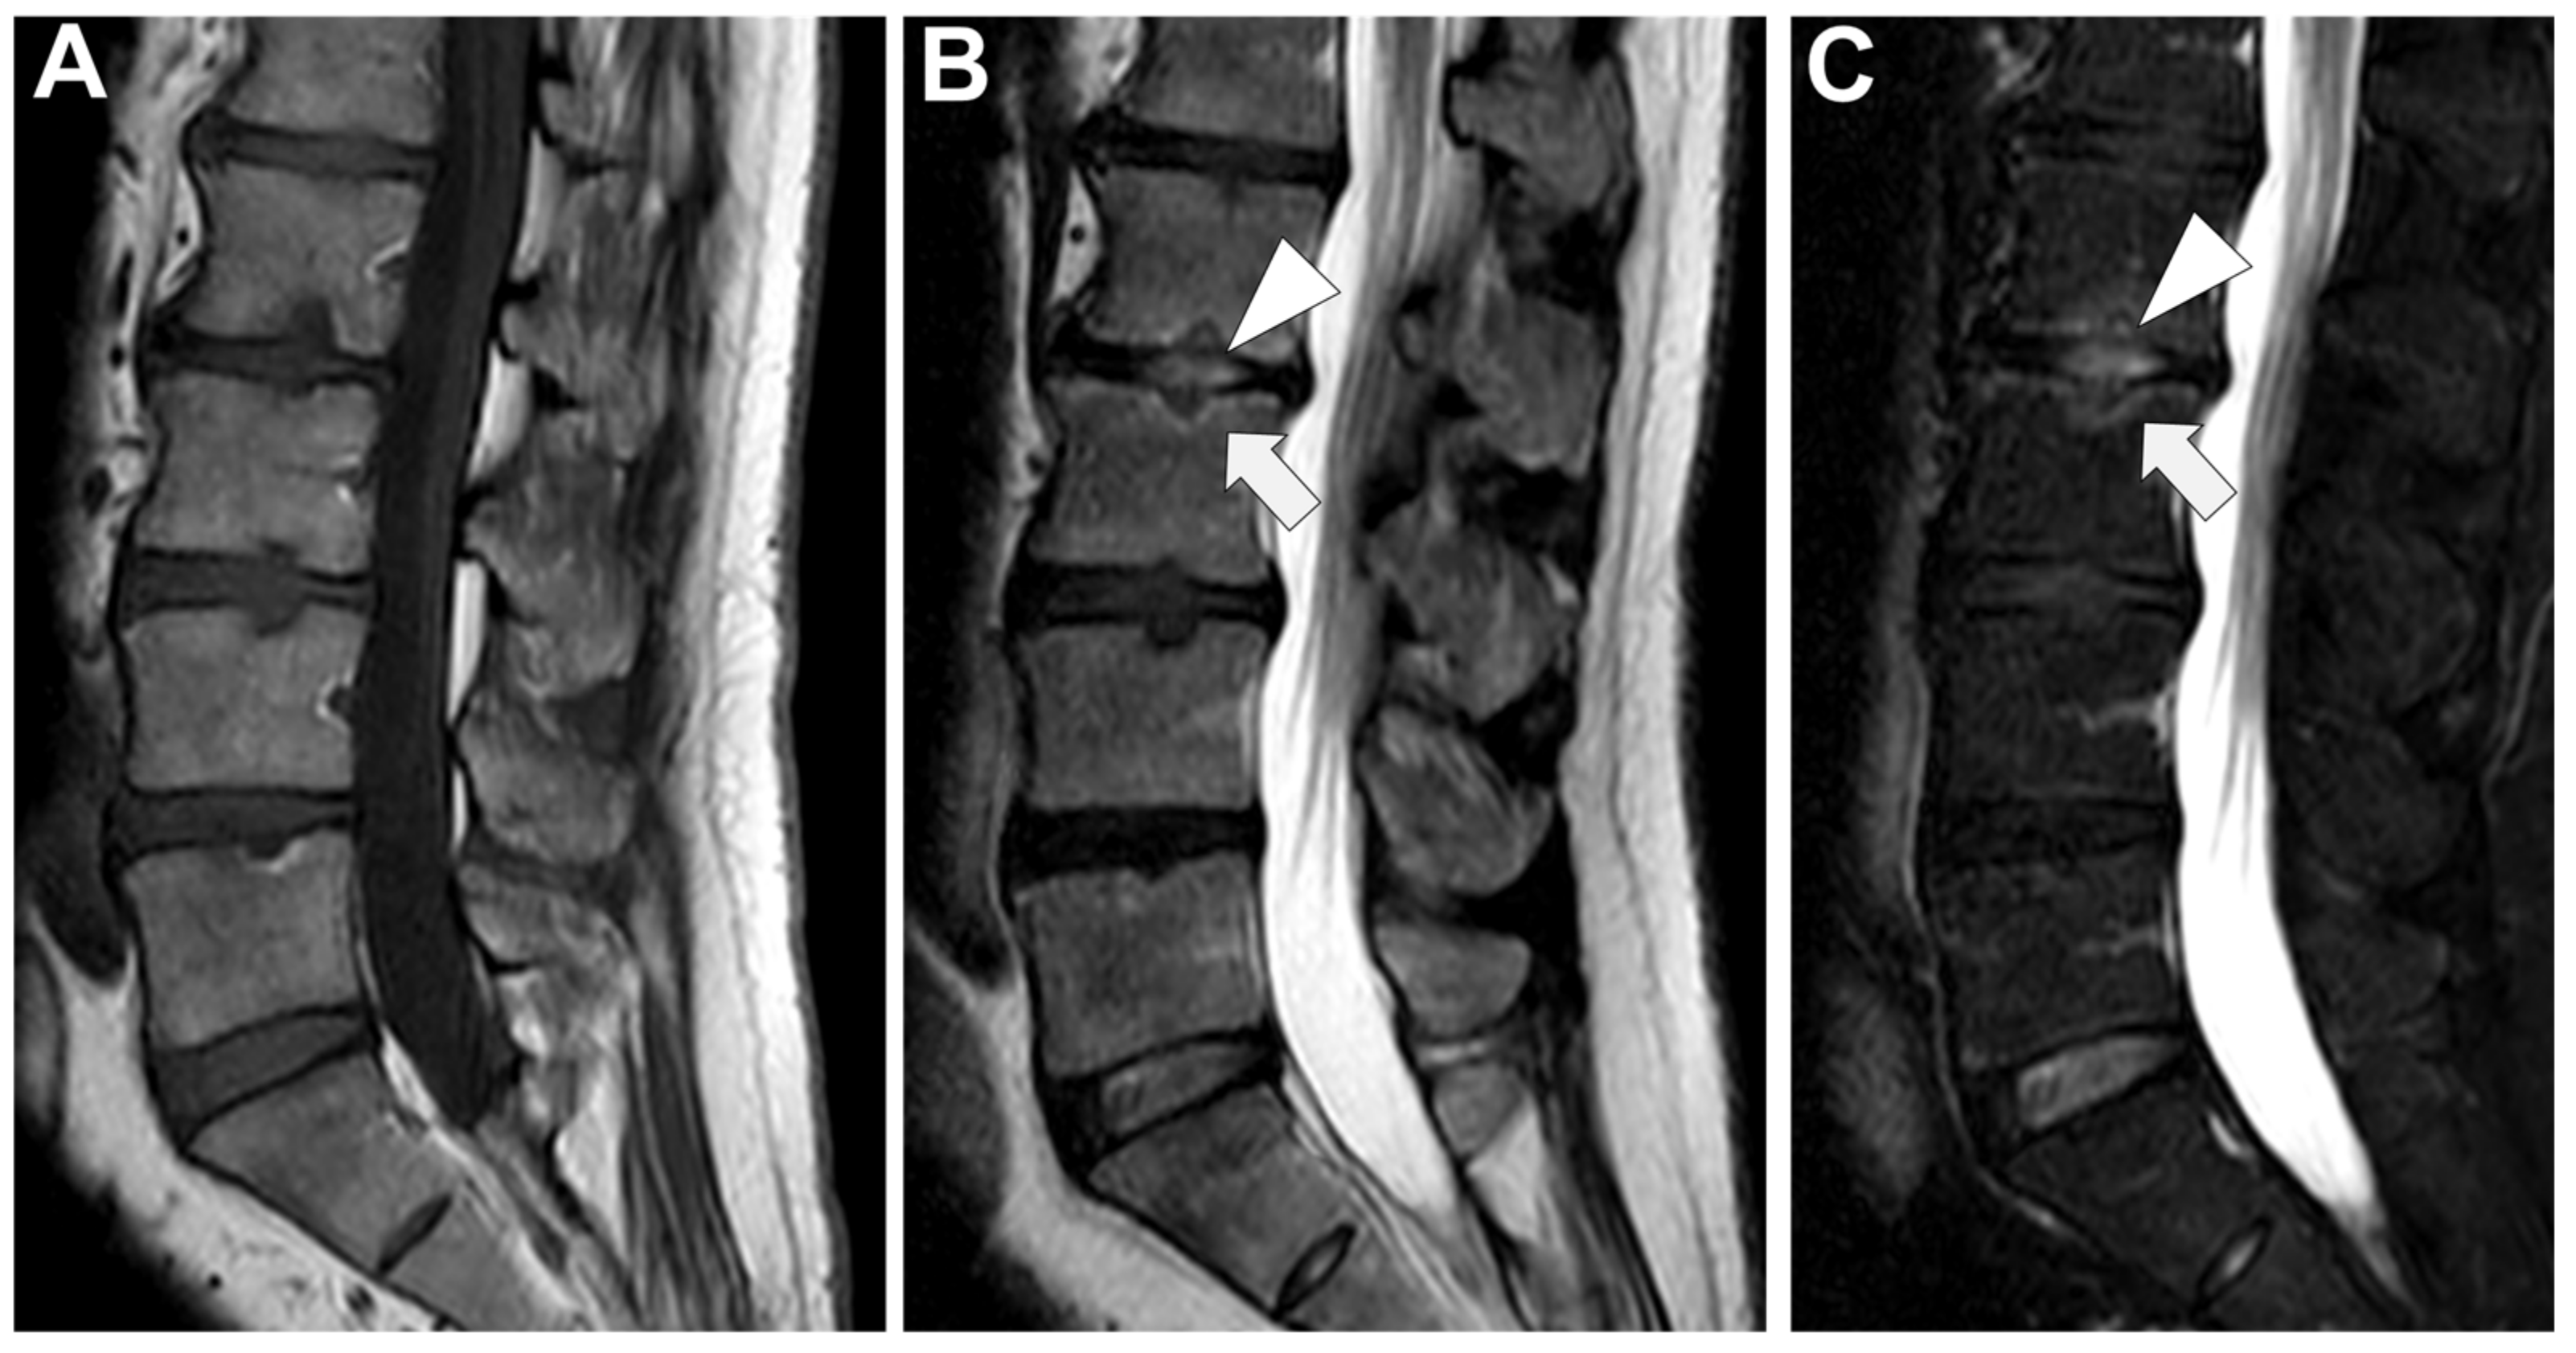

Figure 9. A 56-year-old male presented with a chronic and mechanic lumbar pain. An MRI was performed with (A) T1-weighted imaging (WI), (B) T2-WI, and (C) fat suppressed T2-WI. It demonstrates multiple Schmorl nodes (arrowheads) and a linear high signal intensity (SI) of the subchondral bones on both side of the L2-L3 level (arrows). There was no erosion, small anterior osteophyte, and degenerative disks. Hence, Modic 1 was diagnosed.

Degenerative end plate changes at the early inflammatory phase (Modic 1) can demonstrate some similar radiological features with infectious spondylodiscitis [72,73], that is to say, irregular end plate contours, possible subchondral cysts, and vertebral edema with a horizontal orientation (with high signal intensity on T2-WI—more pronounced with fat suppression method, low signal intensity on T1-WI, and, when performed, possible contrast-enhancement)—Figure 9.

However, additional features can rectify a misdiagnosis. First, the disk thinning is generally extended to the whole disk with low disk signal intensity on T2-WI. Second, on the T1-WI sequence and DIXON fat-saturated sequence, there is still a fatty signal intensity of the end plate. Third, the end plate borders are usually spared and remain continuous. Fourth, the surrounding soft tissues and epidural spaces should be spared. Third, associations with Modic 2 (i.e., healing process with fatty replacement of the vertebral endplate) and Modic 3 (i.e., healing process with sclerosis or hardening of the vertebral end plate) changes are frequent. It must be noted that erosions can happen during this inflammatory degeneration of the disk but without major destruction. Lastly, it has been suggested that DWI could help discriminate Modic 1 from infectious spondylodiscitis, but heterogeneous acquisition parameters have precluded from identifying ADC cut-off with sufficient diagnostic accuracy [74]. However, some qualitative DWI characteristics seem to remain relevant to diagnose Modic 1, such as the ‘claw sign’ [75]. It consists of a linear and paired area with high signal intensity on DWI and well-defined margins, whereas infectious spondylodiscitis would provide ill-defined diffuse (or unpaired) signal abnormalities on DWI [74,75].